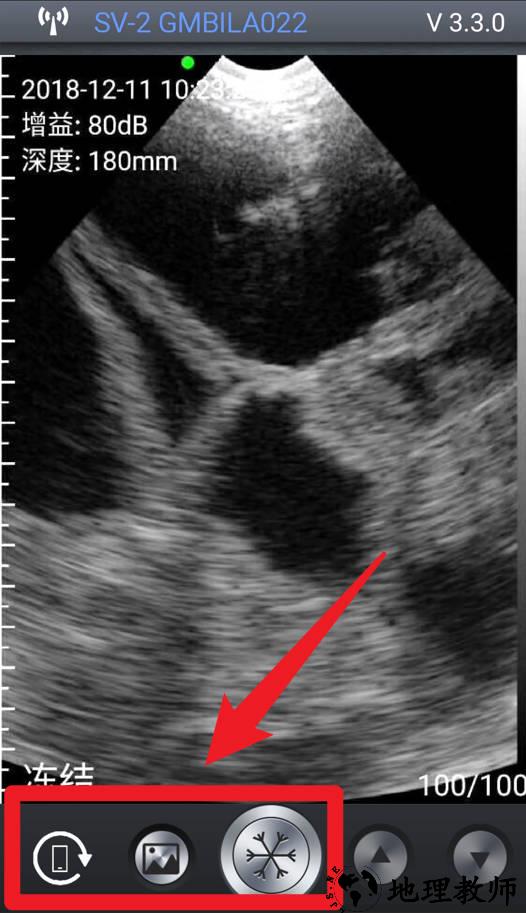

2、点击手机旋转图标,即可进行屏幕旋转控制,适应横屏或竖屏查看,提高操作便捷性。

3、图像处理工具:集成画面放大、对比度调节、区域截图等多种影像增强功能。